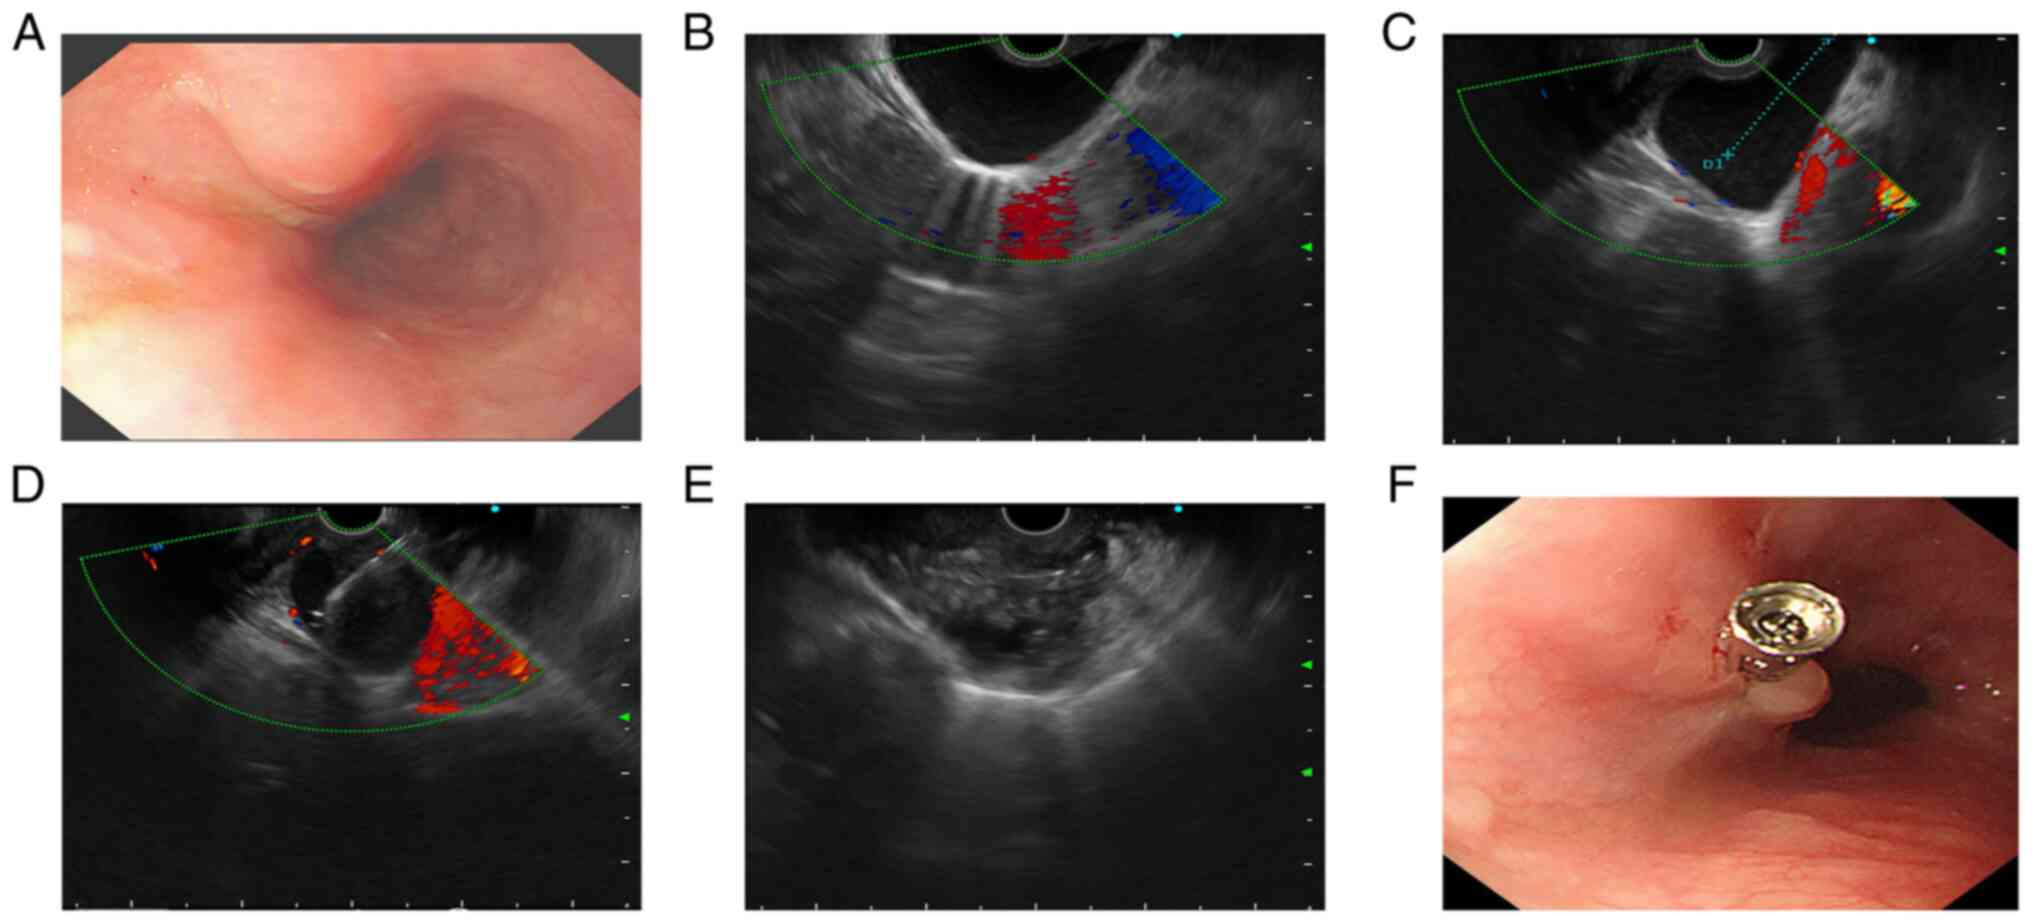

arc-shaped indentation. Endoscopy was performed to clarify further

the relationship between the cyst and the esophagus. Gastroscopy

indicated a strip of submucosal eminence at a distance of 24-40 cm

from the incisors with a smooth mucosal surface (Fig. 3A). EUS (Olympus Ltd) further

revealed a cystic mass of ~6x4.5 cm outside the esophageal wall and

no blood flow signal under color doppler imaging (Fig. 3B).

Based on these findings, cardiothoracic surgeons and

gastroenterologists at our hospital were consulted regarding the

diagnosis and treatment, and the patient was referred to our

department for further treatment after careful consideration. Under

EUS guidance, a 19-gauge needle (Cook Medical, Inc.) was used to

puncture the cyst through the lower part of the esophagus while

avoiding the blood flow signal. Turbid cystic fluid (~40 ml) was

extracted and the capsular wall was lavaged repeatedly with

metronidazole (Sichuan Kelun Pharmaceutical Co., Ltd.) and

anhydrous alcohol, leaving 3 ml of anhydrous alcohol in the cyst. A

small amount of oozing blood was found at the puncture point in the

lower part of the esophagus and a titanium clip was used to clamp

the puncture point (Fig. 3C-F).